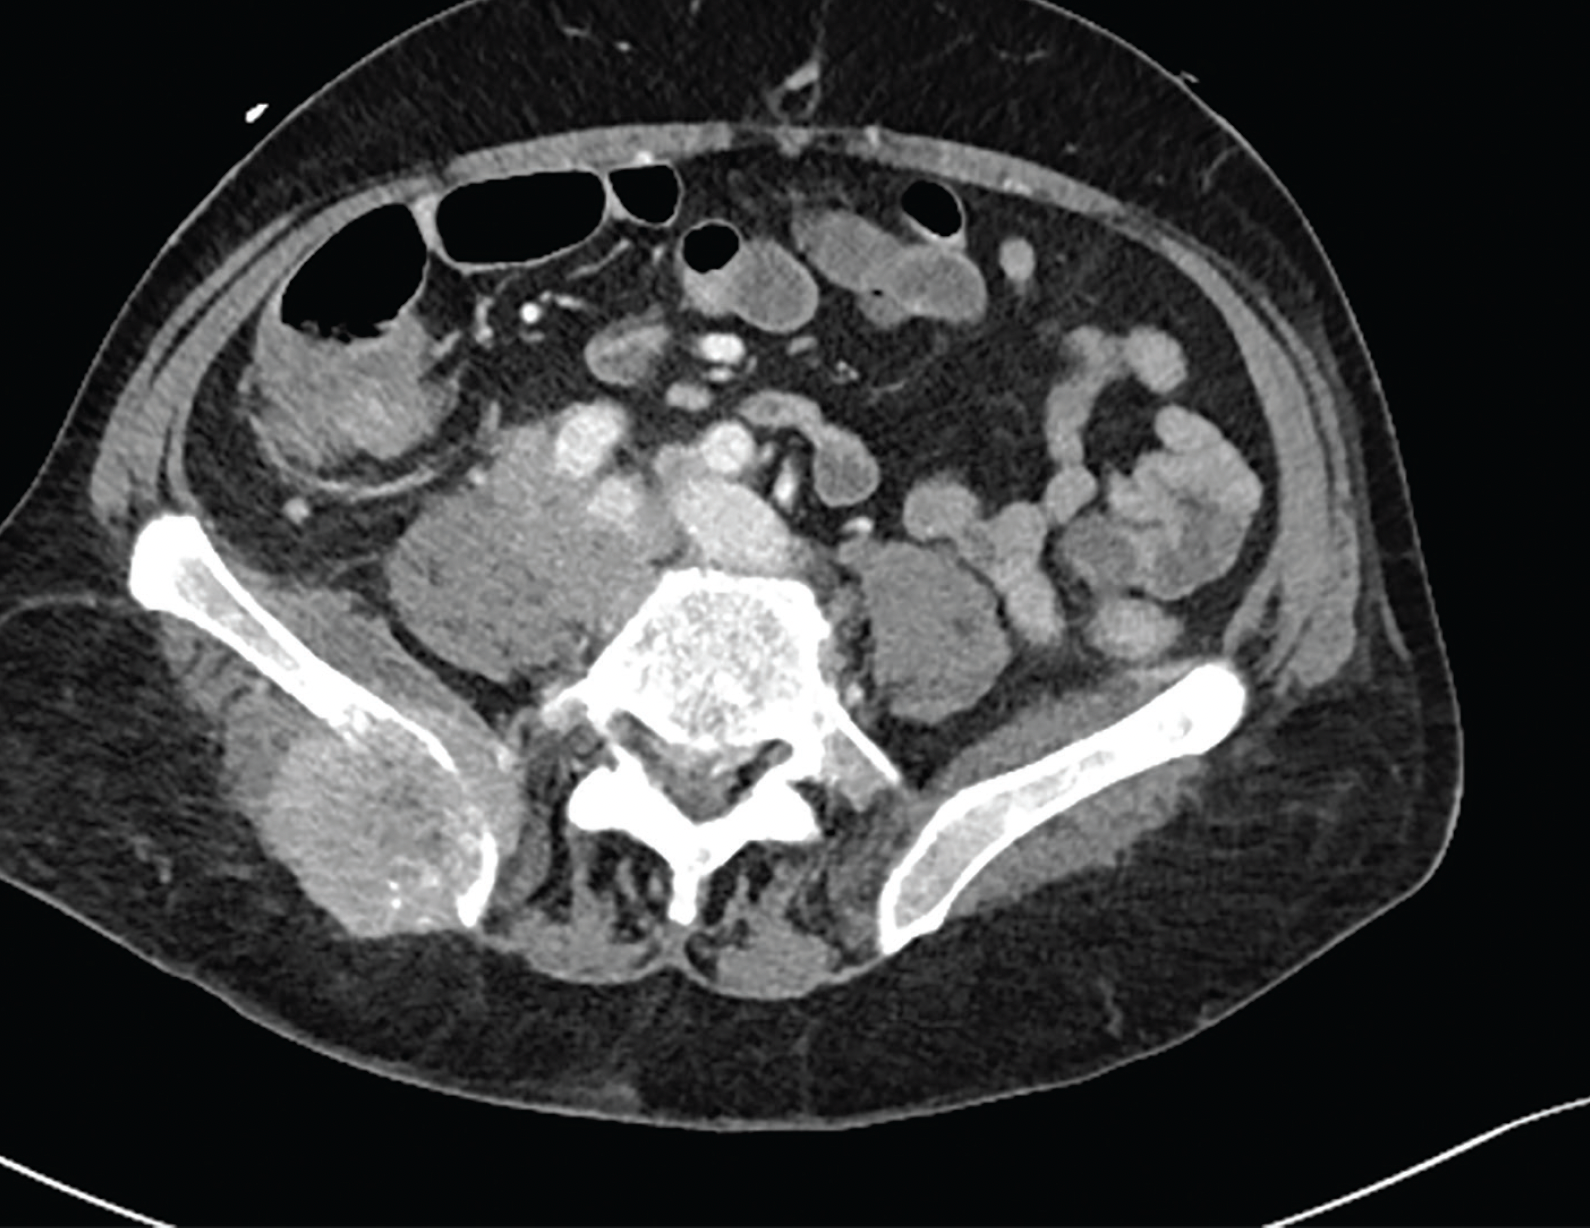

PATIENT CASE.

FIGURE 1.

FIGURE 2.